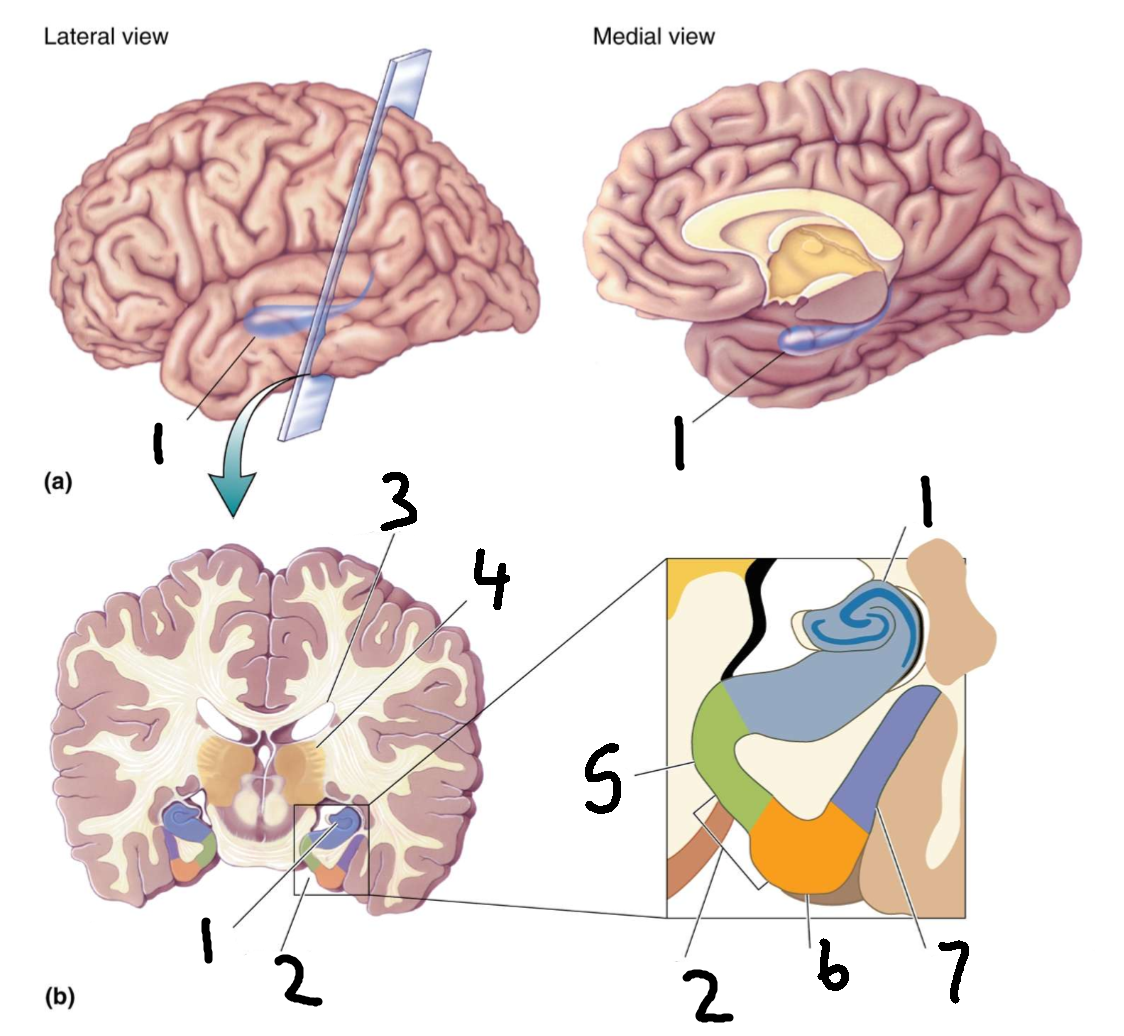

What is 1?

cingulate gyrus

What is 2?

corpus callosum

What is 3?

fornix

What is 4?

cut edge of midbrain

What is 5?

parahippocampal gyrus

What structure is this?

hippocampus

What is 1?

hippocampus

What is 2?

rhinal sulcus

What is 3?

lateral ventricle

What is 4?

thalamus

What is 5?

entorhinal cortex

What is 6?

perirhinal cortex

What is 7?

parahippocampal cortex